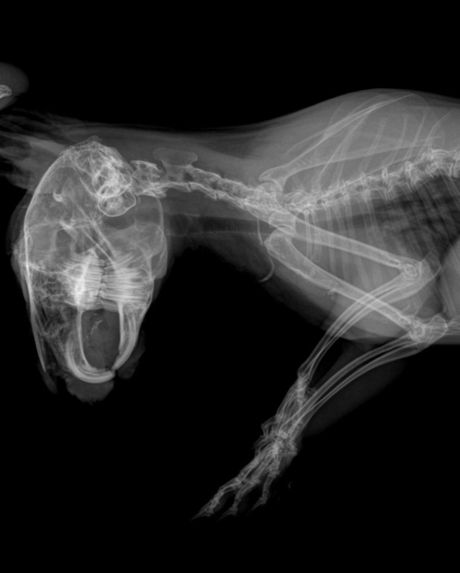

Oboleli kunić Foto: Facebook/Privatna arhiva/Mia Lazović

Kunić nije dobro, jer mu gornji zubi rastu nagore i pritiskaju očnu jabučicu čime mu povređuju oči, ustanovljeno je na rendgenskom snimku. Žena koja trenutno brine o kuniću kaže da su veterinari posavetovali da životinju odnese na Veterinarski fakultet u Beogradu kod veterinara specijalizovanog za egzotične životinje. Rendgen, bris i terapije su plaćeni zahvaljujući ovoj dobrotvorki, ali je sada potrebna pomoć da se kunić transportuje u Beograd.